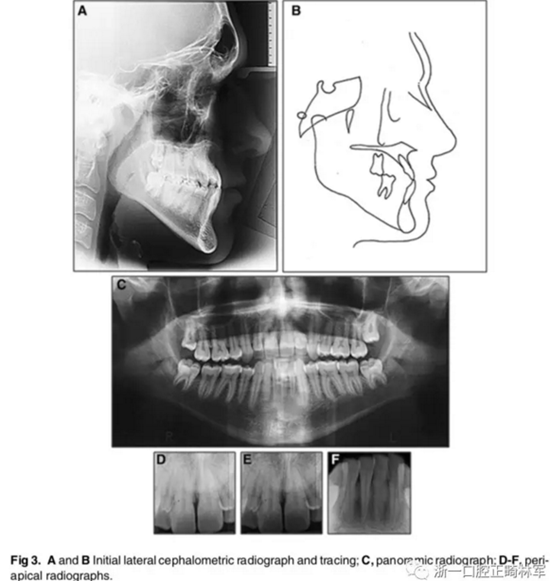

影像檢查:

X片示:III類頜骨關(guān)系(ANB,-4°;Wits值,-10mm);上切牙前突、唇傾,下切牙內(nèi)縮(1:NA, 8mm、35°; 1:NB, 4mm、15°;IMPA, 77°);綜合考慮咬合平面角、下頜平面角、Y軸角,判定為水平生長型;McNamara分析示,上頜相對顱底后縮(Co-A, 88mm; A-NPerp, 4mm),下頜相對顱底前突(Co-Gn, 135mm; Pog-Nperp, 10mm),上下頜骨不調(diào)(Co-A–Co-Gn, 47mm);此外,患者4個第一前磨牙缺失。